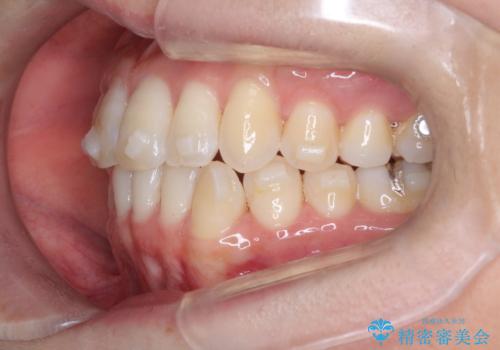

【インビザライン】前歯の凸凹をなおしたい

- 前歯の凸凹を主訴に来院されました。

上顎の急速拡大を行なったのちインビザラインにて治療を行なっております。

今回のケースは後戻りのリスクを低くし、またディスキング量を減らすために上顎の急速拡大を行なっております。